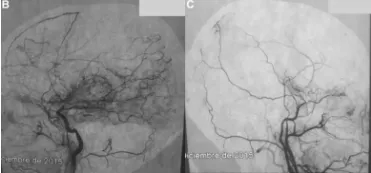

针对纯海绵窦内表皮样囊肿,何种手术入路能在手术相关并发症...